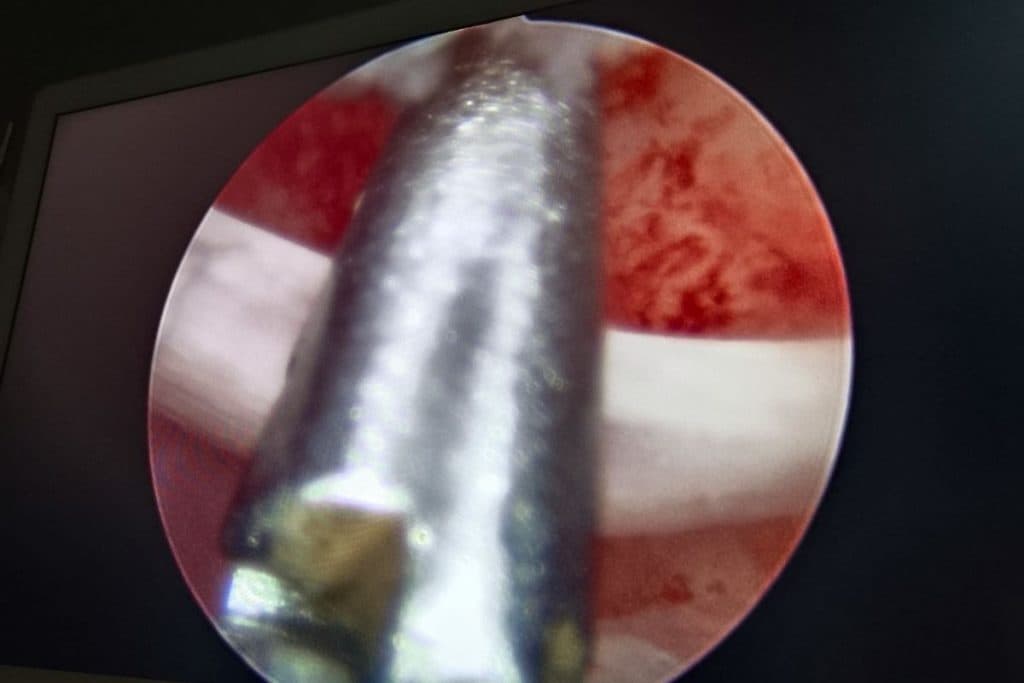

महिला की बच्चेदानी से निकाली गई हड्डियां (बायें) और (दायें) कम्प्यूटर स्क्रीन पर ऑपरेशन के लिए बच्चेदानी में किया गया छिद्र.

डॉ अपेक्षा साहू ने जरूरी जांच करने के बाद महिला की बच्चेदानी में फंसी सारी हड्डियों को निकाल दिया. बिना पेट में कोई चीरा लगाये दूरबीन पद्धति से महिला का उपचार किया गया. दो नर्सों की मदद से डॉ अपेक्षा साहू ने महिला की बच्चेदानी से सारी हड्डियां निकालीं. हड्डियां निकाले जाने के बाद महिला पूरी तरह से स्वस्थ है. सुबह में उसका उपचार करने के बाद शाम में अस्पताल से छुट्टी भी दे दी गई.